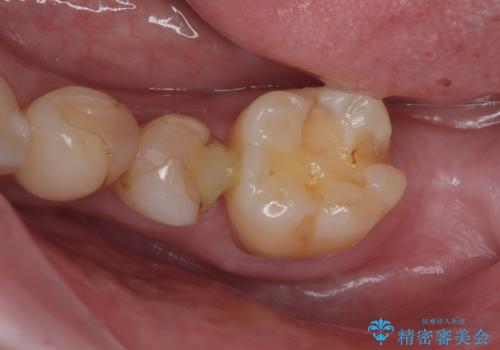

詰め物が外れかけてるのでやり替えたい セラミックインレー修復・フルジルコニアクラウン